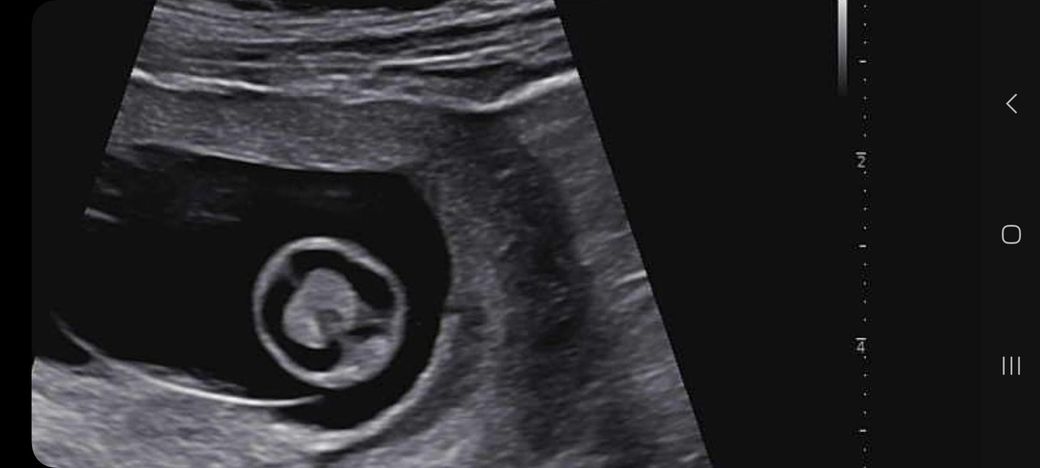

임신 10주차가 되었고 오늘 초음파 사진을 찍고왔어요

다 잘 크고있는데

머리 뇌 모양이 나비 모양이 아니라

2주뒤에 초음파 사진 볼 때 한번 더 보자 하더라구요

나비 모양이 되야 정상? 인데 아니라 신경이 쓰이네요

어떻게 보시는지 의견을 들려주심 감사합니다.

• 1번 째 사진